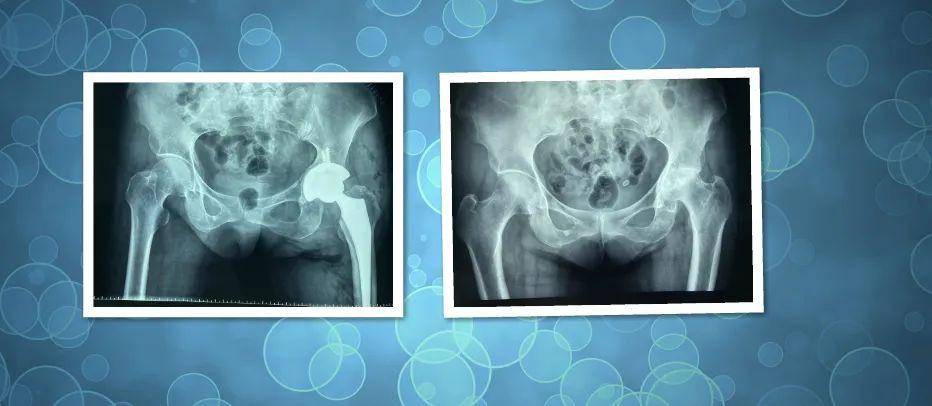

【武安一院】妙手仁心展风采 精湛医术正伤骨---祝贺骨三科成立3周年

武安一院妙手仁心展风采精湛医术正伤骨祝贺骨三科成立3周年